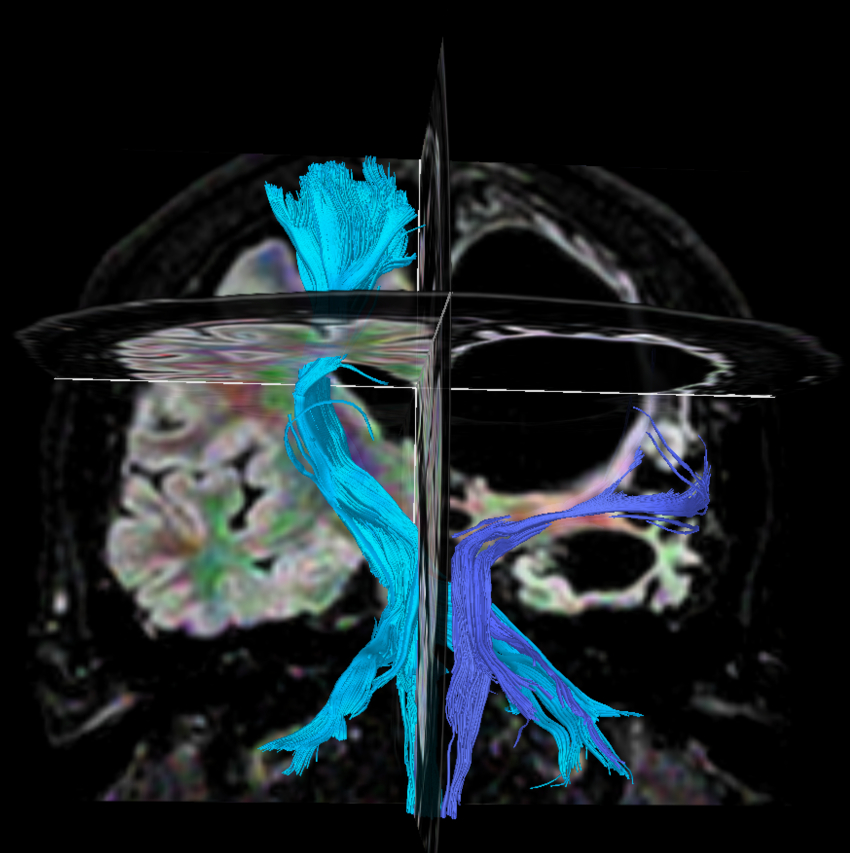

Axial DTI FiberTrak (32 directions)

DTI FiberTrak (32 directions)